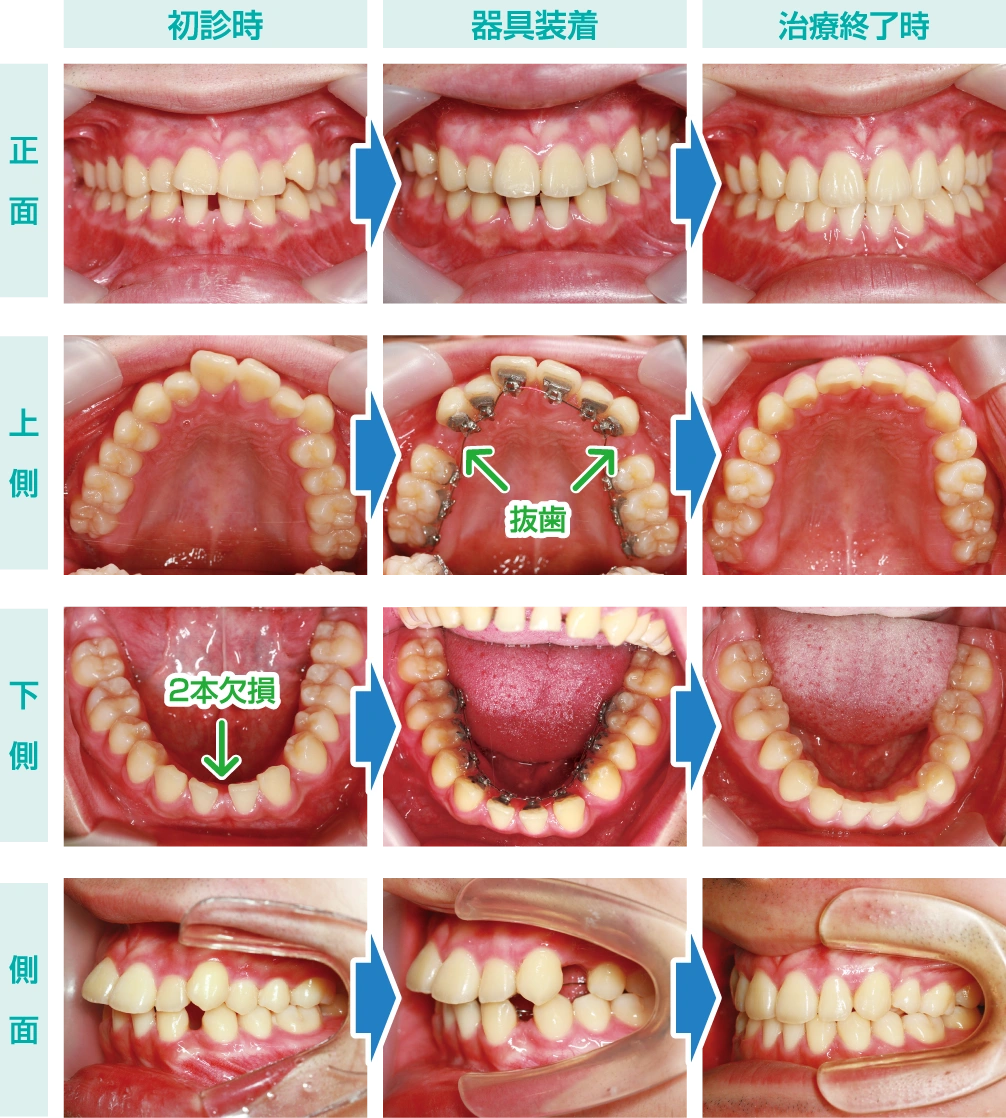

患者様は16歳の男子。上顎前歯の凸凹と下顎前歯のスペースを治したいという主訴でした。

生まれつき下顎前歯の2本が欠損しているためスペースが生じており、上顎は凸凹の叢生改善と上下の咬合を良好にするため、上顎第一小臼歯を2本抜去しました。

そして上下顎にデジタル処理されたリンガルブラケットを装着して歯列全体のコントロールをしていきました。

下顎のスペース閉鎖及び上顎の叢生改善と抜歯スペースの閉鎖が完了して、ブラケットを外しました。1年10ヶ月の治療期間を要しましたが、他人に気づかれずに矯正ができたメリットは大きいでしょう。